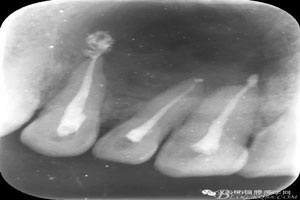

圖2.抗感染治療一周后,行11、12、13根管治療術(shù)。